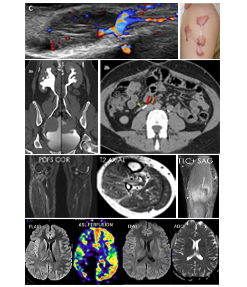

Stay up to date with the latest advancements in radiology. Read our exclusive newsletters, case studies and research papers authored by leading doctors.